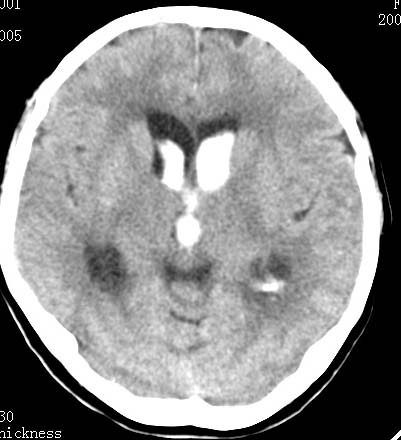

男性 病人 请大家看看出血的部位究竟在哪里?

是不是脑室系统出血啊! 伴轻度脑积水! 请老师指教!!

原发性脑室出血!

脑室系统出血,并脑积水.

我觉得是左侧侧脑室体旁出血,破入脑室系统.理由:除了左侧脑室体部外缘不规则之外,还有就是左侧脑室里面出血量较右侧多!

应该是左侧侧脑室内的出血导致其他脑室内的积血。

应该是尾状核出血破入侧脑室.

1、原发脑室出血,出血部位应该是左侧侧脑室;

2、左侧基底节区腔隙性脑梗塞;

(不考虑脑积水,脑室急性出血期脑室系统会轻度扩张)

脑室系统出血,第三脑室,侧脑室都有

出血点在左侧脑室旁。

左侧尾状核体部出血破入脑室系统.

最重要的是要讲明以脑室内积血为主,脑积水